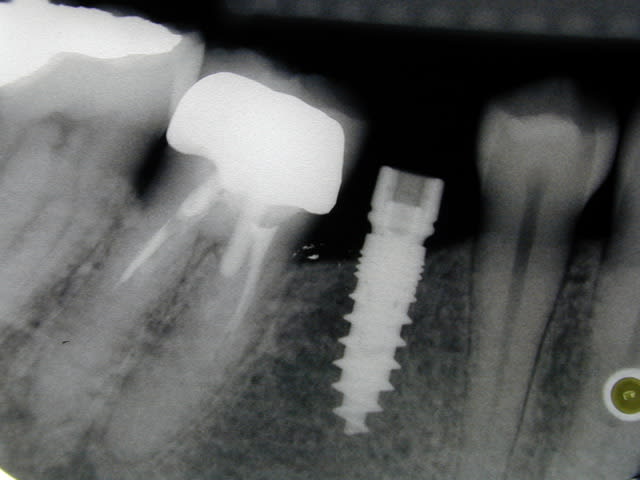

C1 ka6uqo - Eugenol

C2 vatgl6 - Eugenol